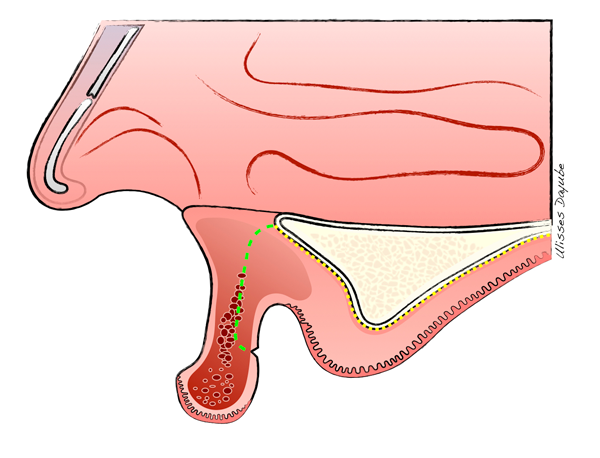

O defeito vertical severo do rebordo maxilar anterior representa um dos cenários clínicos mais desafiadores da regeneração óssea. Portanto, para obter resultados satisfatórios, é necessária uma abordagem precisa, por meio da combinação de aumento ósseo vertical e manipulação de tecidos moles. Aqui, será descrita uma técnica para tratar deficiências verticais severas na maxila atrófica anterior (Figuras 1) usando membrana de politetrafluoroetileno denso (PTFE-d) e enxerto ósseo particulado heterógeno. A manipulação do tecido mole deverá ser utilizada para superar as desvantagens do aumento vertical do osso (por exemplo, perda da profundidade vestibular e mucosa queratinizada).

Entretanto, é de suma importância a correta e precisa abordagem cirúrgica, no que tange à incisão do rebordo alveolar. Nesse procedimento, foi realizada uma incisão “invertida”, que seria uma modificação da técnica de Kazanjian1. Uma incisão labial foi realizada perto do limite do vermelhão do lábio (Figuras 2 e 3), produzindo um retalho de base palatina, o que é indicado sempre que há necessidade de aumento substancial na altura do rebordo maxilar anterior (Figuras 4 e 5).